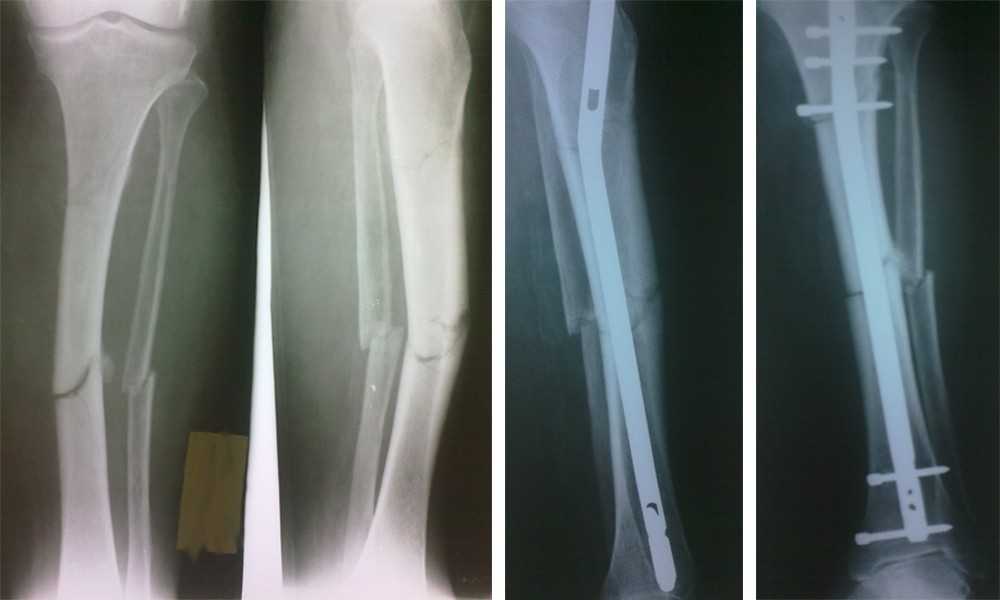

Лечение трещины кости ног